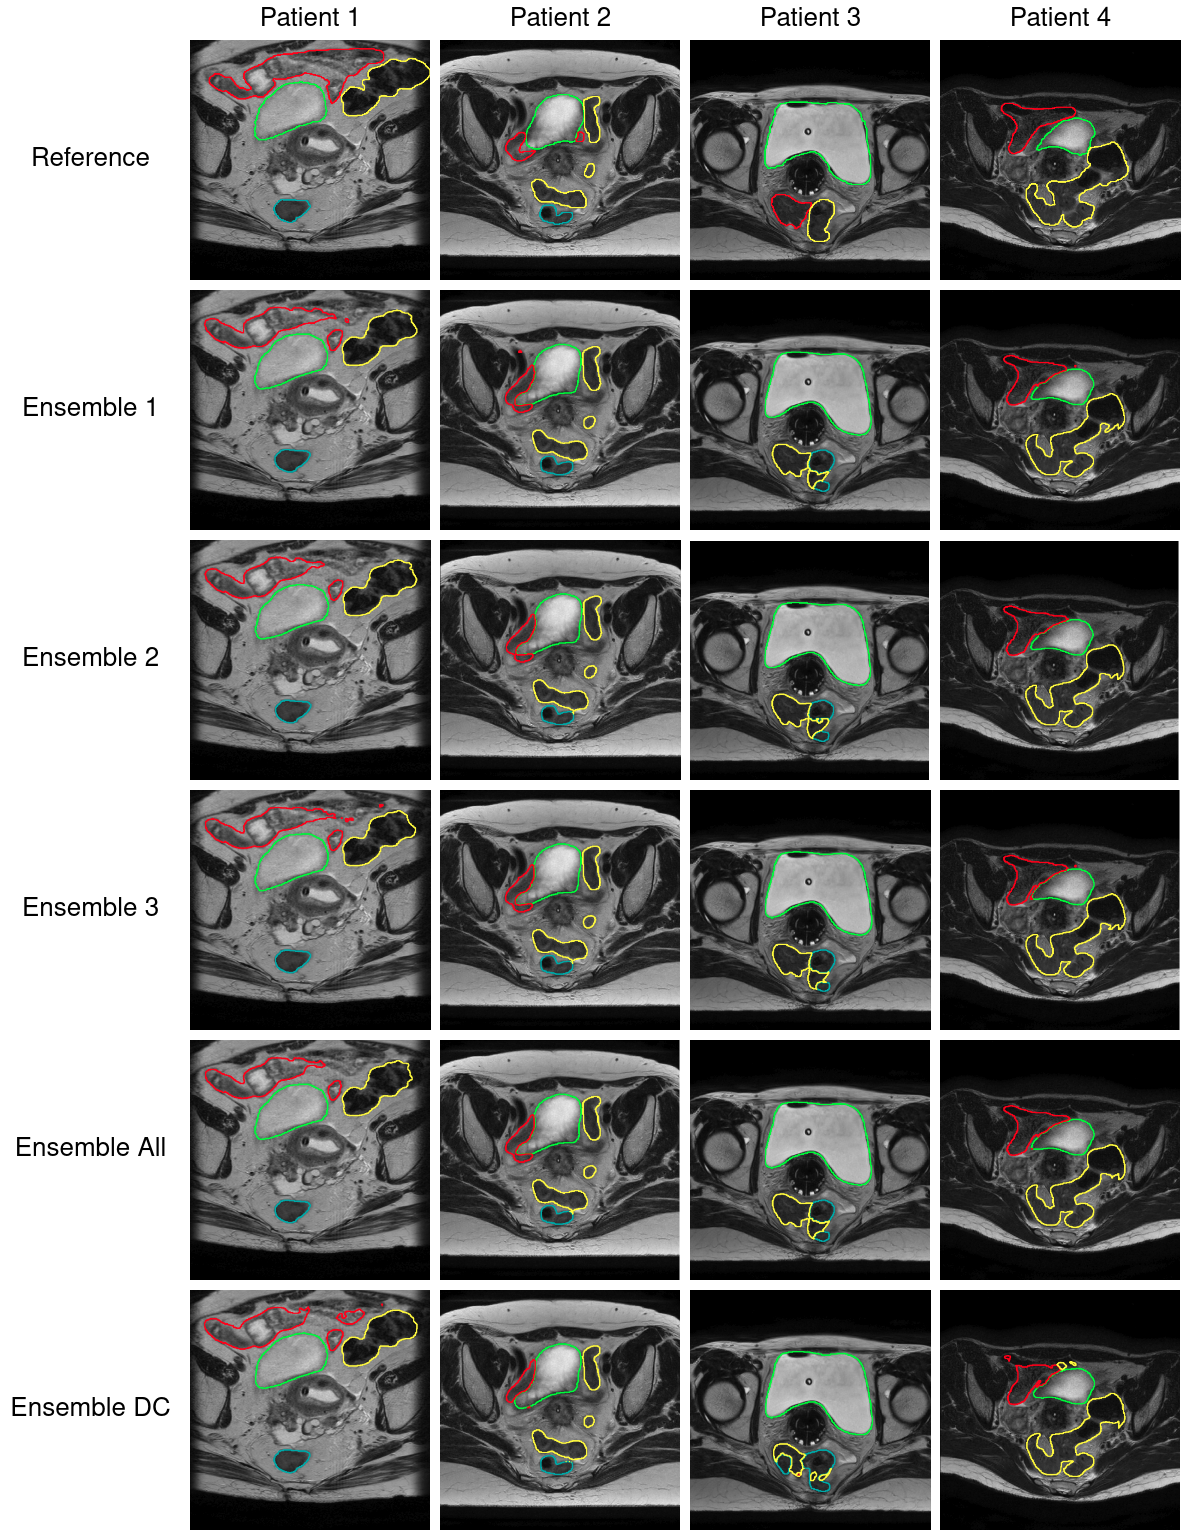

In Table 2 the results from the 5-fold experiments of every single model, but also from the ensemble experiments are presented. The combination that achieves the best performance according to the average metrics (i.e., averaged over all OARs as presented in the Avg column in Table 2) is referred to as Ensemble 1 (DeceptiConv, SwinConvNet, CUnet, Swin UNETR, and U-Net), followed by Ensemble 2 (DeceptiConv, SwinConvNet, CUnet, Swin UNETR, U-Net, and UNETR), Ensemble 3 (DeceptiConv, SwinConvNet, CUnet, Swin UNETR, U-Net, and MSUneTr), and finally Ensemble All (all 7 models). The ensemble from the 5 DeceptiConvs is referred to as Ensemble DC.

For visualization purposes, we calculate the average Dice Coefficient of every model, for every round in their 5-fold experiment, resulting in 5 scores per model. Then we average all these values for every fold, resulting in 5 final values. We sort them, and keep the fold that corresponds to the median of these values, which in our case was the 2ndsuperscript2𝑛𝑑2^{nd} fold. We randomly selected 4 patients from the validation set of this fold, from which we then selected 1 slice from each patient based on the reference that contains a lot of information. The results are presented in Figure 7 and Figure 8.

Refer to caption

Figure 8: Predictions of ensembles of models on the Cervical Cancer Dataset. Green: bladder, Red: bowel, Cyan: rectum, Yellow: sigmoid.

The visual results of the predictions of the models, and the Dice scores between their predictions (most of them achieving >0.82absent0.82>0.82 Dice score) also indicate a high similarity in performance, but at the same time every model makes different mistakes. We can observe a high confusion of the models when predicting the sigmoid, bowel, and rectum, for the reasons we mentioned earlier. In order to mitigate this problem, it might be wise to follow a different approach than trying to segment the OARs separately (e.g., segment these three organs as one organ and then separate them). Nonetheless, to eventually decide which model is better in practice and whether its results are clinically acceptable, we have to conduct validation studies with doctors, something we are planning to do in the near future.